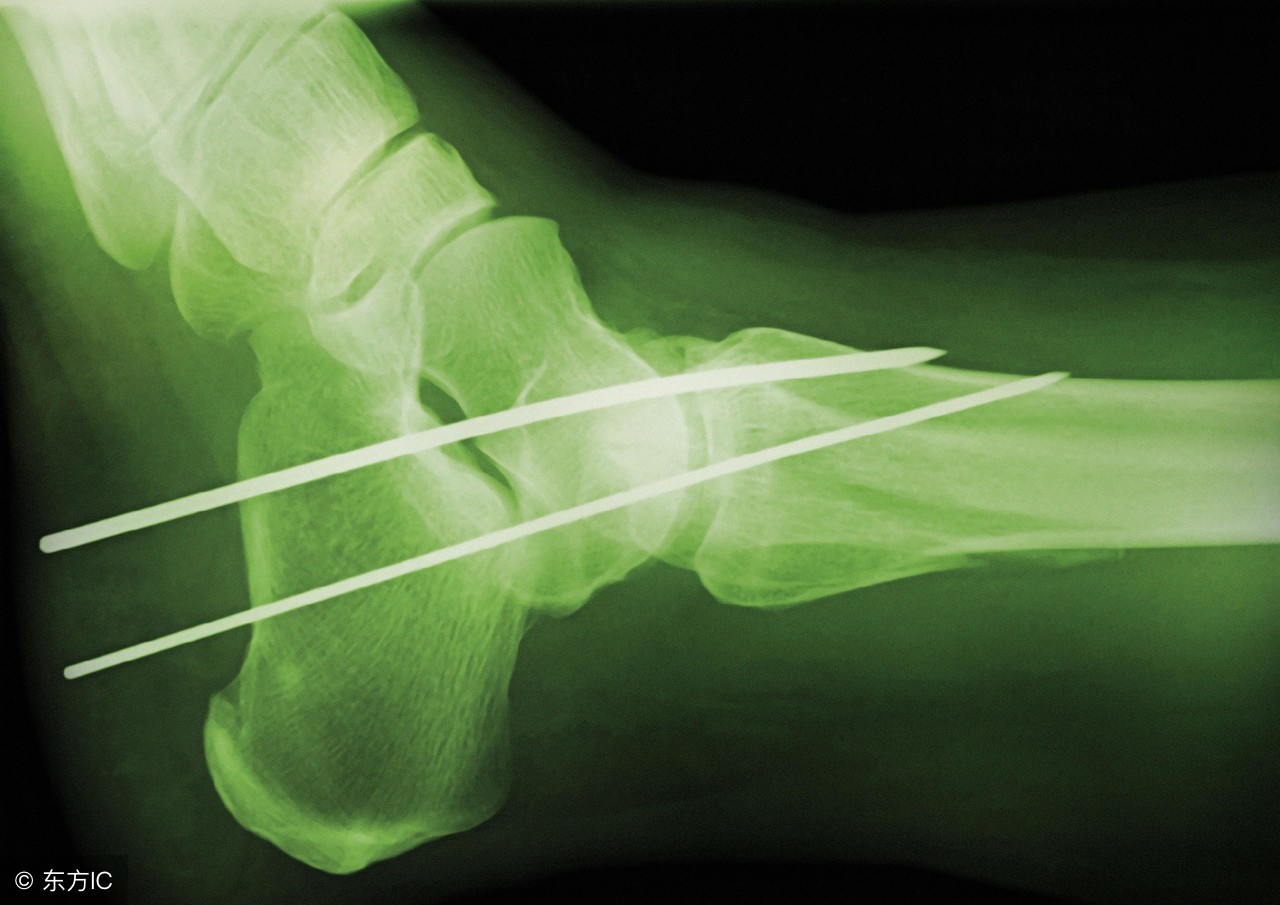

常见的不完全性骨折只需石膏固定即可愈合,但完全性骨折病情较重,即骨的完整性和连续性全部中断,处理此类骨折常需要通过手术治疗,在断骨连接处采用钢板和钢钉牢固的固定住错位断骨,使之对线对位,有助于断骨的生长及愈合,从而避免对线、对位不正而导致的畸形。

当骨折彻底愈合后可依据病情拆除钢板、钢钉。